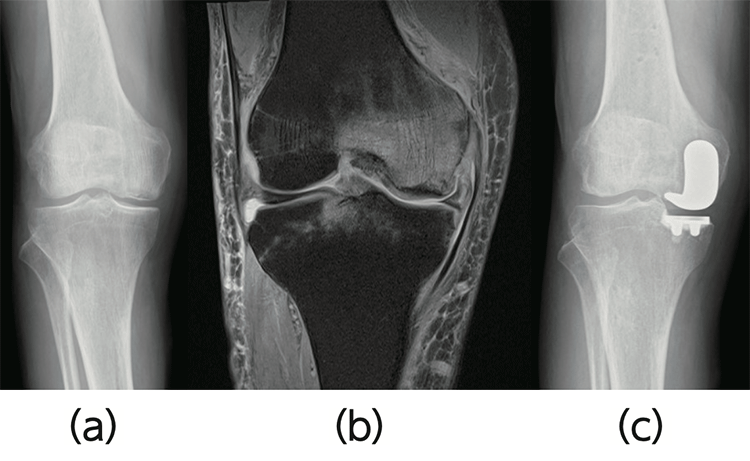

- ・人工膝関節単顆置換術(たんかちかんじゅつ)(図2)

- 変形が膝関節の片側に限られ、関節内のそれ以外の部位の変形が軽度な高齢者に行います。

大腿骨内側顆骨壊死による変形性膝関節症(a:単純X線画像、b:MR画像)に対し、部分的に人工関節インプラントで置換します(c)